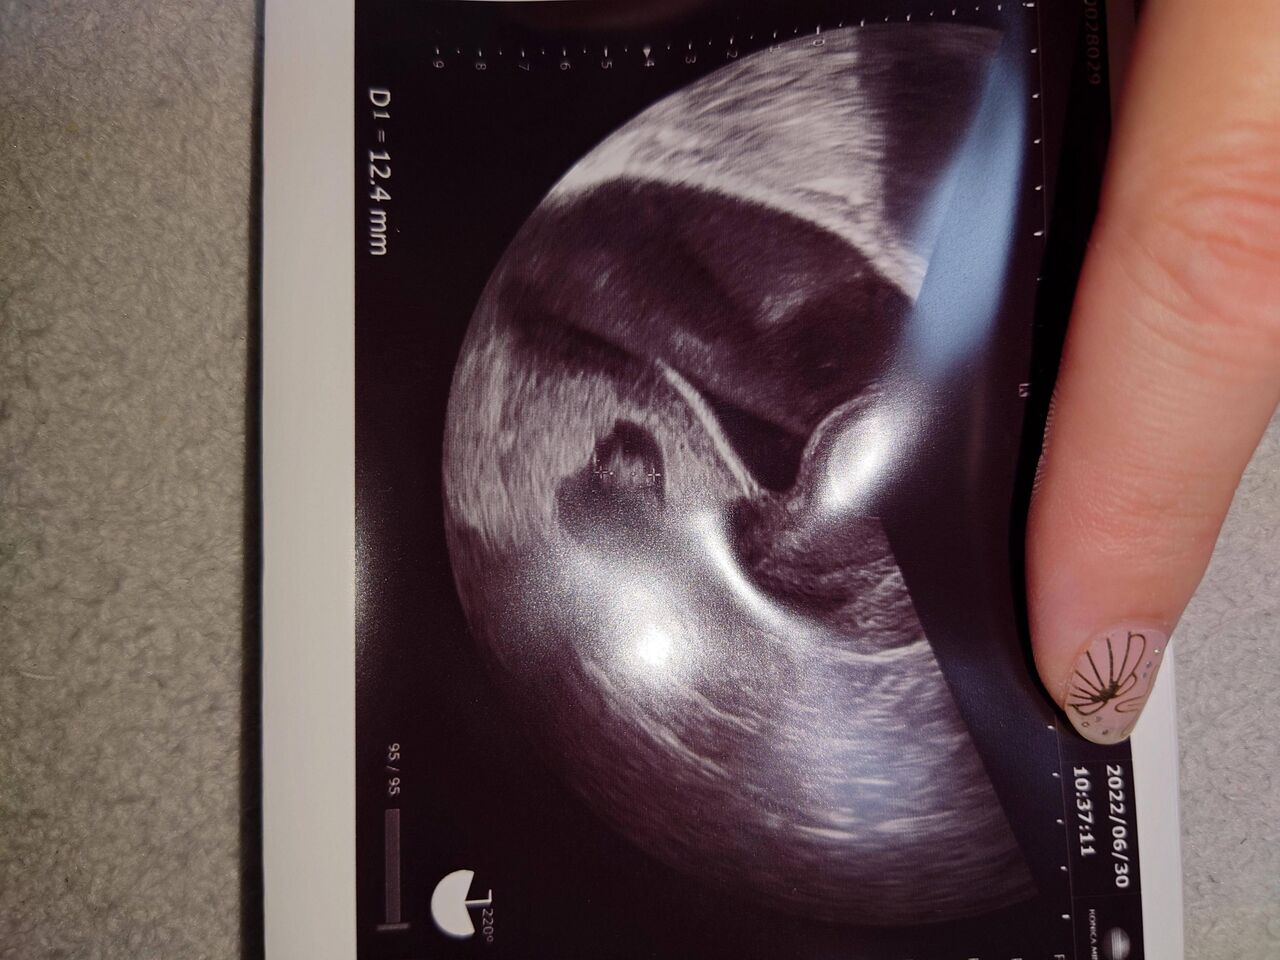

それにしても卵管結紮してても子供できちゃうとか珍しいんだって